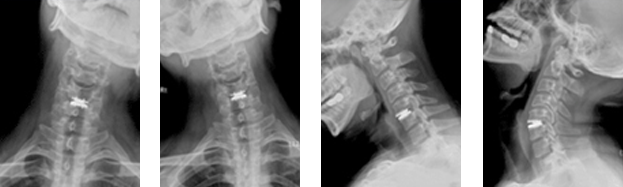

목인공디스크치환술이란?

목디스크 제거 공간에 뼈이식을 해서 수술한 마디를 굳혀주는(글 유합술) 치료법이다. 가장 표준적인 치료법이지만 골유합술은 목 운동을 일부 제한하게 되고 그에 따라서 몇 년간 시간이 지나면서 주변 관절의 퇴행성 변화를 촉진할 가능성이 높은 것이 문제점으로 지적되어 왔습니다. 최근 소개된 목 인공디스크 치환술은 디스크를 감압 제거한 후 마디를 굳히는 대신에 특수하게 제작된 인공관절역할을 하는 인공디스크를 이식하여 수술 후에도 목의 운동이 제한되지 않도록 하는 수술법입니다.

• 이후 정확한 위치에 인공디스크를 삽입하기 위해서 영상증폭장치(C-arm)등을 이용해서 위치를 실시간으로 확인하면서, 디스크가 제거된 빈 공간에 알맞은 크기의 인공디스크를 삽입합니다.

목인공디스크치환술 수술 후 목인공디스크치환술 수술 후